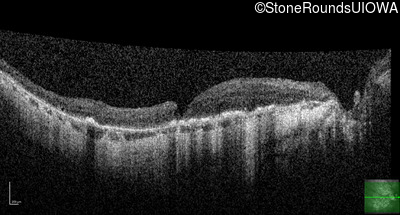

This 81 year old man began using a flashlight to read menus in his 40's. At age 75 his ophthalmologist noticed abnormal fundus findings and referred him to a retina specialist.

| Age at visit: 81 years |

| Age at visit: 82 years |

| Age at visit: 83 years |

| Age at visit: 84 years |

| Age at visit: 85+ (Visit 1) |

| Age at visit: 85+ (Visit 2) |